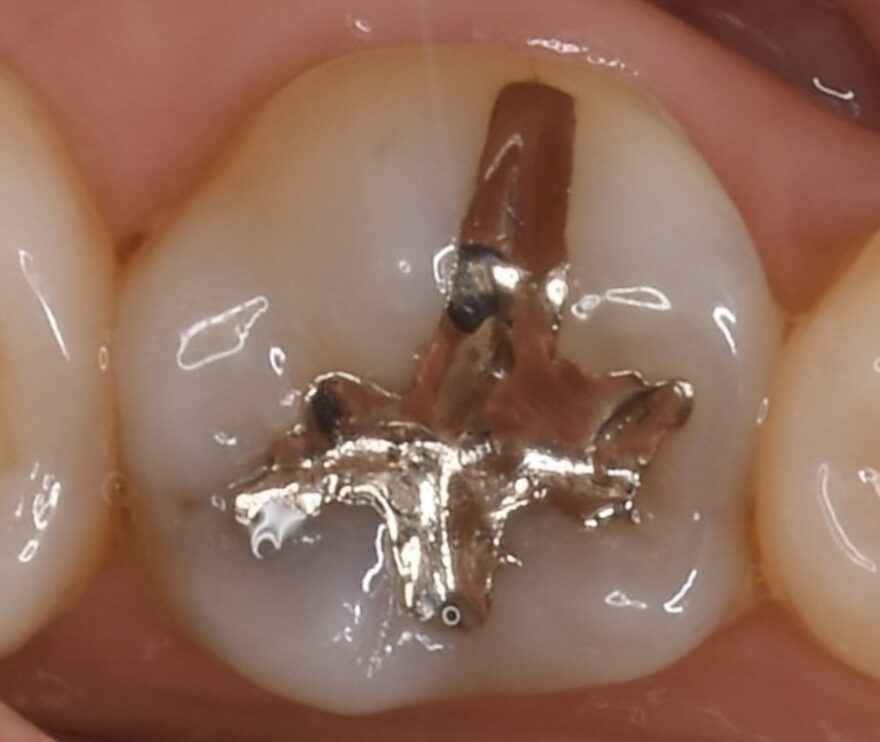

①銀歯の中でまた虫歯になってしまう。

銀歯は金属なので、噛む力で少しづつ変形していきます。

変形してできた隙間に汚れが溜まりやすくなるため、虫歯菌が銀歯の内部に侵入していきます。

しかし、銀歯の内部は定期検診時にレントゲン撮影をしても、虫歯の進行を確認できません。

そのため、気が付かないうちにどんどん虫歯が進行し、最終的には神経を失う事態になることもあります。

銀歯内部の虫歯をセラミックで修復した治療例

治療前後の経過写真

症状が全くなくても、銀歯を入れてから5年以上経過していると、深部でむし歯が再発していることがほとんどです。

銀歯は劣化が早く、隙間から細菌が侵入することが、むし歯再発の原因です。